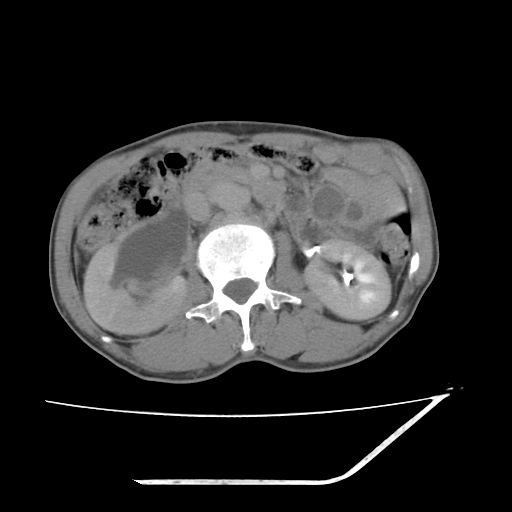

平扫

考虑右肾盂癌,肾动脉受侵,右肾功能减退,右肾盂输尿管积水,管壁增厚,考虑种植转移,应该把下面扫完的

支持右侧肾盂癌伴肾静脉瘤栓形成可能性大,右肾结石.肝右叶后段低密度影,不除外转移.

考虑右肾盂癌,肾动脉受侵,右肾功能减退,右肾盂输尿管积水,管壁增厚,考虑种植转移  支持

右肾盂旁ca并肾静脉瘤栓形成/肾功能降低。

右肾结石。

右肾盂癌,肾动脉受侵,右肾盂输尿管积水,管壁增厚,考虑种植转移

右肾盂移行细胞癌并右输尿管中段转移.肾积水.

支持 右侧肾盂癌伴肾静脉瘤栓形成可能性大,右肾结石;肝右叶后段低密度影,不除外转移。

1.右侧肾盂癌伴肾盂积水。

2.肾脏功能减退,原因有:(1)肾动脉受侵。(2)肾静脉受侵(3)肾积水,等。本例,肾动脉显影较好,但受压明显;肾静脉无明显显示,受压或静脉癌栓,下腔静脉腔内未见明显充盈缺损。

3.右侧上段输尿管扩张,原因:(1)积水所致;(2)种植。